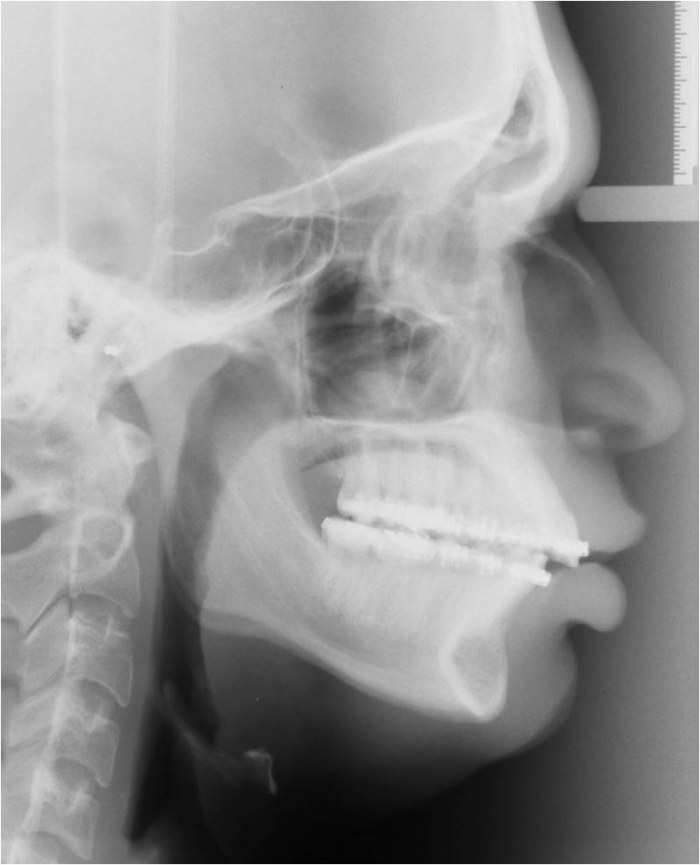

Telerradiografia inicial